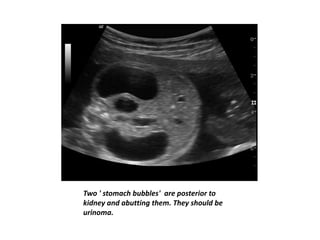

Two ' stomach bubbles' are posterior to

kidney and abutting them. They should be

urinoma.